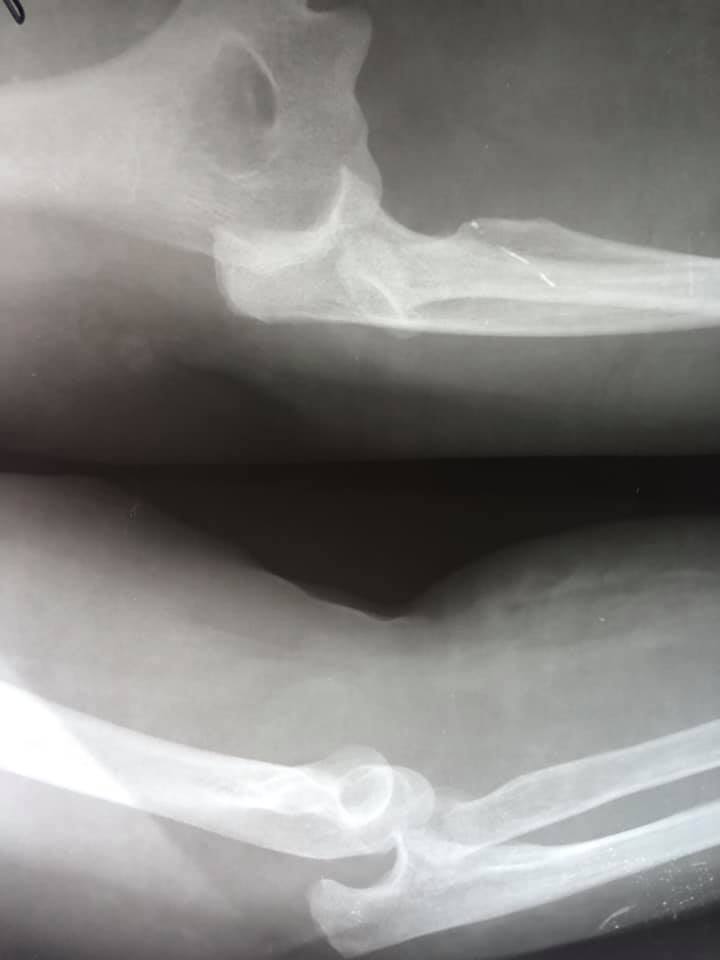

В ургентному порядку жінка звернулася в КНП «НЦМЛ». Після огляду був встановлений діагноз: травматичний вивих кісток правого передпліччя з повним відривним відламковим переломом голівки променевої кістки. Йдеться на сторінці медзакладу.

Проведена відкрита репозиція перелому та вивиху з внутрішньою фіксацією. В операційній працювали лікарі-ортопеди-травматологи: Родзь Тарас Яремович; Брус Роман Богданович. Анестезіологічне забезпечення Піддубний Юрій Федорович, лікар-анестезіолог; Бадзюнь Лілія Любомирівна, сестра медична-анестезистка. Магдюк Людмила Анатоліївна, сестра медична операційна.